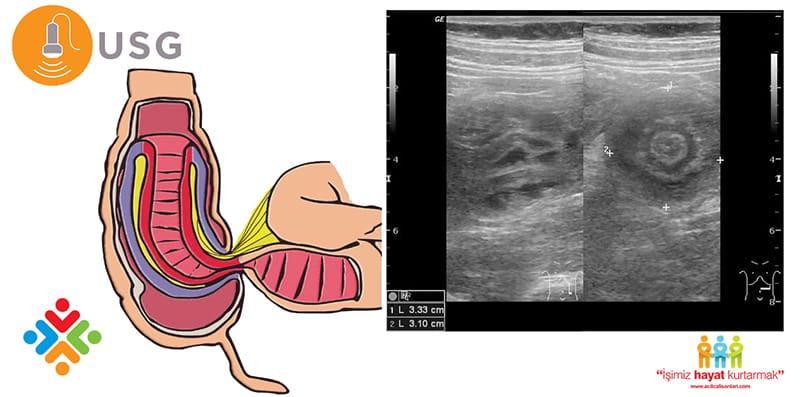

Ultrasonografi :

Ultrasonografi duyarlılığı ve özgüllüğü, deneyimli bir ultrasonografın elinde %100’dür. Deneyimli bir sonograf tarafından yapılan bir çalışmanın negatif

öngörü değeri de yaklaşık %100’dür.

Ultrason, fluoroskopik tekniklere göre patolojik başlangıç noktalarını daha iyi tespit edebilir, bir redüksiyon prosedürünün başarısını izlemek için kullanılabilir. Ultrason aynı zamanda apandisit veya hidronefroz gibi çocuğun semptomları için çeşitli alternatif nedenler için de değerlendirebilir.

• İnvajinasyonun ultrason üzerindeki klasik tezahürü, bağırsaktaki bağırsak katmanlarını temsil eden bir hedef işaretidir. En yaygın tip olan ileokolik intususepsiyon için, hedef işareti genellikle sağ alt kadrandadır. Sağ alt kadranın (örn., Paraumbilikal veya sol abdominal bölgede) dışında invajinasyonun lokalizasyonu ile ince barsak invajinasyonun olasılığı önerilmektedir.